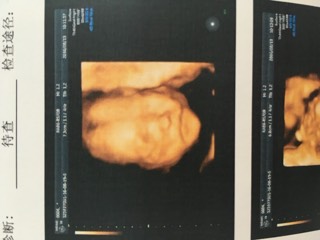

公立医院提前两个月都约不到四维,只好去私立医院做了,老公可以进去陪同哟,我躺着,他坐旁边,我们面前一个大的屏幕,医生在肚子上探测,屏幕上就出现宝宝动态,看的好清楚,医生在照宝宝腿的时候给了两个镜头,我看到中间那一小坨了,哈哈,老公看不懂,只有医生带着说的时候才知道哪是哪,笨!小猴子一开始不太配合,老用手遮住脸,后来医生在别处按了下才让他变了下动作,整个过程差不多20多分钟,也算顺利吧,把结果给家人看,都说宝宝像我,这下巴和嘴巴像极了,哈哈,就是小猴子在肚子里瞎动,脐带绕颈一圈,医生说不要紧,现在宝宝还小,等28周左右的时候再看,希望到时候小猴子可以顺顺利利的哟。